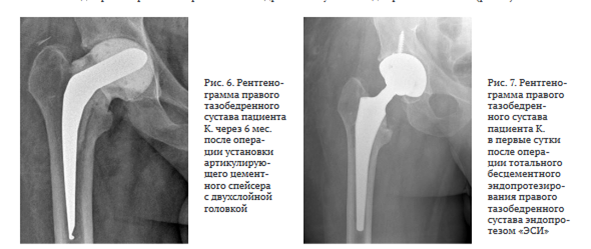

10.10.2023 произведена операция в объеме: удаление артикулирующего спейсера, тотальное бесцементное эндопротезирование правого тазобедренного сустава эндопротезом «ЭСИ» (рис. 7).

Через 12 мес. после второго этапа эндопротезирования в объеме удаления артикулирующего спейсера, тотального бесцементного эндопротезирования левого тазобедренного сустава Beijing Montagne Medical device / Zimmer функциональные показатели сустава пациента по шкале HHS — 89, по шкале WOMAC — 14, выраженность болевого синдрома по шкале ВАШ — 1 балл. Рентгенограмма представлена на рис. 8.

Через 12 мес. после операции тотального бесцементного эндопротезирования правого тазобедренного сустава эндопротезом "ЭСИ" функциональные показатели сустава по шкале HHS — 91, по шкале WOMAC — 11, выраженность болевого синдрома по шкале ВАШ — 0 баллов. Рентгенограмма представлена на рис. 9.